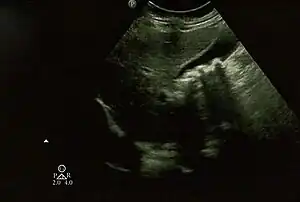

| Biliary pseudolithiasis as seen on ultrasonography. The gallbladder contains gallstone mimics resulting from ceftriaxone therapy. |